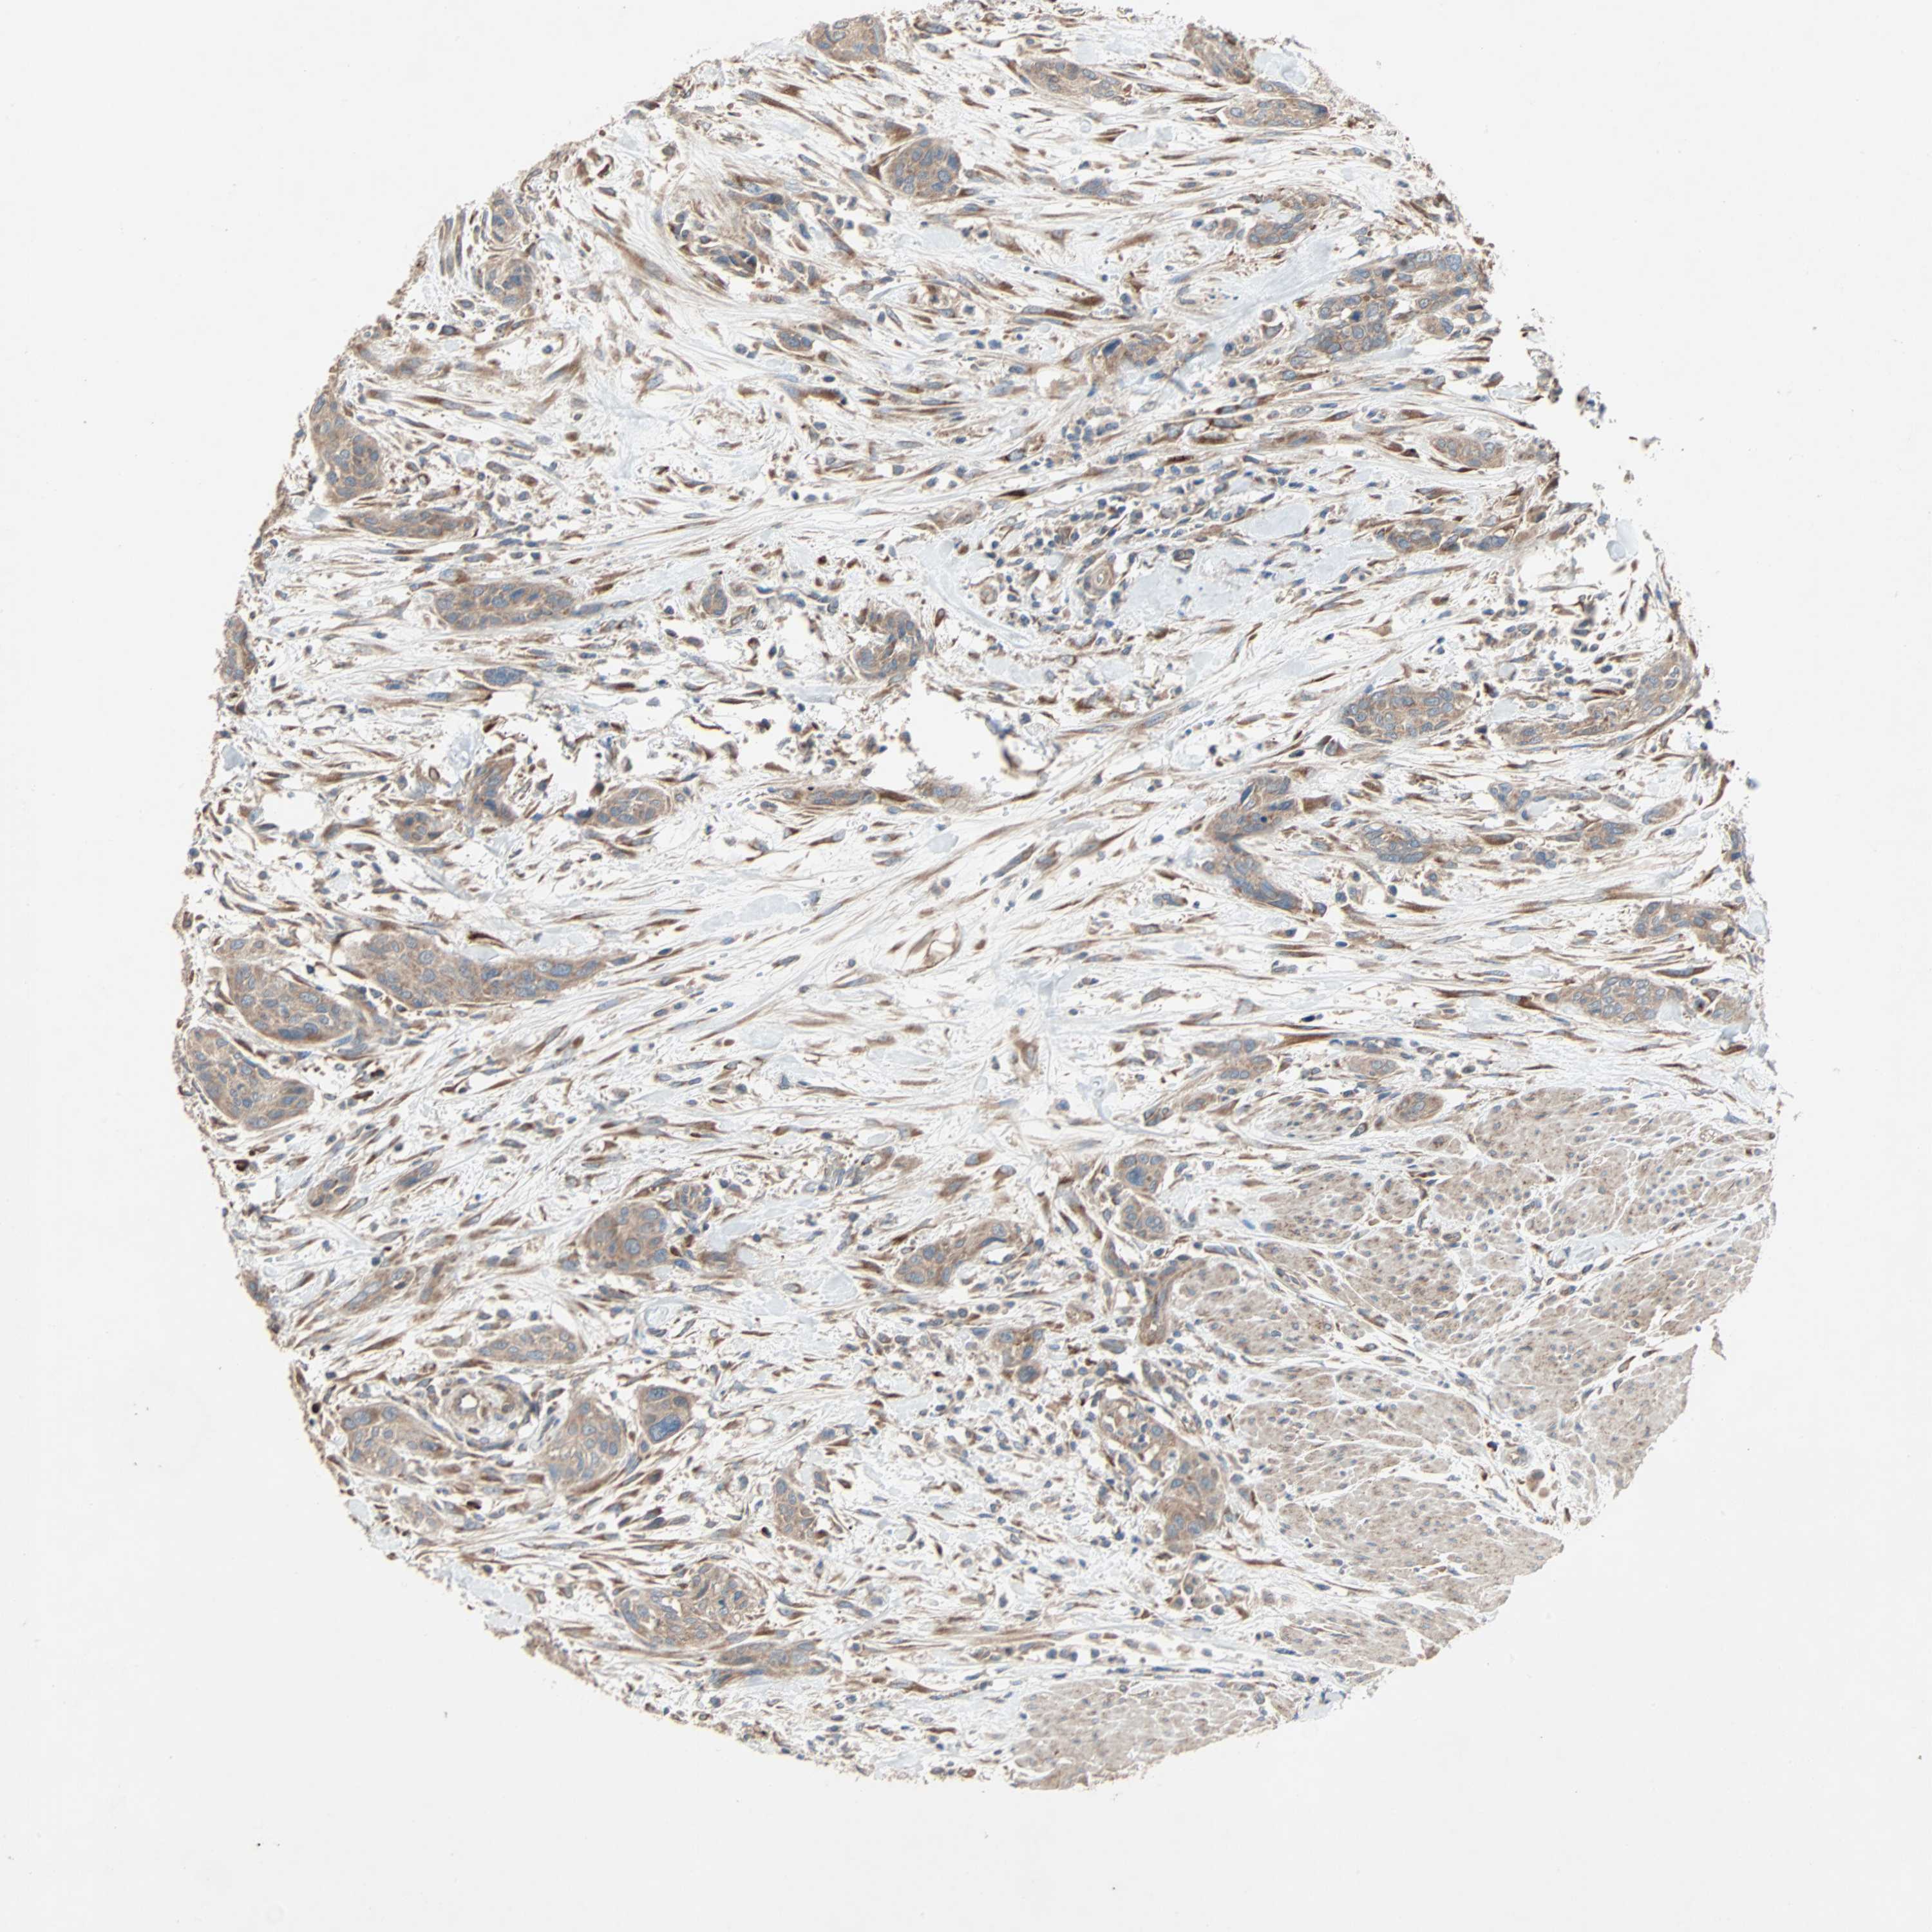

UROTHELIAL CANCER - Protein expressioni

A mouse-over function shows sample information and annotation data. Click on an image to view it in a full screen mode. Samples can be filtered based on level of antibody staining by selecting one or several of the following categories: high, medium, low and not detected. The assay and annotation is described here.

Note that samples used for immunohistochemistry by the Human Protein Atlas do not correspond to samples in the TCGA dataset.

Antibody stainingi

Antibody staining in the annotated cell types in the current human tissue is reported as not detected, low, medium, or high, based on conventional immunohistochemistry profiling in selected tissues. This score is based on the combination of the staining intensity and fraction of stained cells.

Each image is clickable and will lead to virtual microscopy that enables deeper exploration of all samples and also displays staining intensity scores, fraction scores and subcellular localization as well as patient and tissue information for each sample.

Antibody HPA007478

Antibody HPA007966

Urothelial carcinoma, Low grade

Urothelial carcinoma, High grade